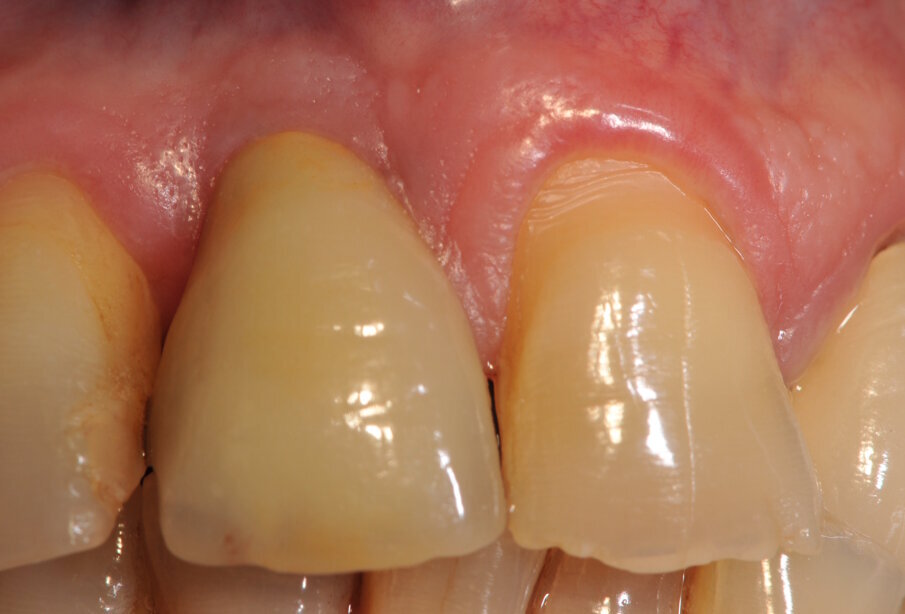

Fig. 5_Moncone Easy slim angolato, notare la quantità di tessuto cheratinizzato dopo condizionamento funzionale con corona provvisoria a pontic.

Fig. 9_Situazione clinica prima della cementazione della corona definitiva.

Fig. 10_Corona definitiva appena cementata con tecnica extraorale.

Fig. 11_Corona definitiva a 1 mese dalla cementazione.

Fig. 12_Corona definitiva a 1 anno dalla cementazione. Notare la chiusura degli spazi interprossimali.

Fig. 14_ Corona definitiva a 4 anni dalla cementazione. Notare la stabilizzazione dei tessuti molli.

Fig. 16_Stabilità dei tessuti molli perimplantari a 4 anni.